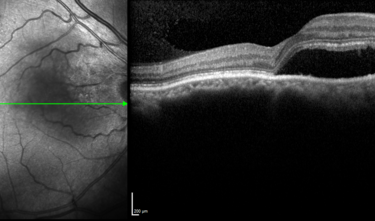

Clase 21 - Desprendimiento de vítreo y desprendimiento de retina

Clase 20 - Signos clave en patología traccional vítrorretiniana

Clase 18 - Signos estructurales diferenciales entre neurodegeneración y exudación en DMAE